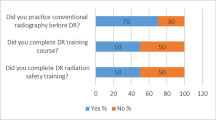

In the present study, a number of phantom images of the lateral aspect of the femur were taken with certain positioning errors to determine the minimum exposure dose for a pre-test image. In the sample images with positioning errors, observers were asked to measure error distances ΔX and ΔY from a complete overlap between inside and outside of the dry bone specimen, as shown in Fig. 1a, b, respectively. Three RTs participated in the observer study to measure error distances ΔX and ΔY on the images taken at different levels of pre-test exposure (10, 5, and 2% of the actual exposure dose). Figure 2 shows the alignment of an X-ray tube, objects, and a detector (FPD). We used two water equivalent phantoms as scatterers. The total thicknesses of the water phantoms (10 cm) were empirically determined from the standard thickness of knee joints. To represent various types of positioning errors, sample images were taken in the following three positions: 1: lateral rotation and a slight adduction; 2: medial rotation and clear abduction; and 3: a slight medial rotation, as shown in Fig. 3.

3.3 Determination of the pre-test exposure dose rate for checking patient positioning

The column (a) in Fig. 4 shows the radiographic image of dry bone specimen of a femur exposed to standard exposure dose in the hospital. The columns (b), (c), and (d) in Fig. 4 show the images obtained at 10, 5, and 2% of the standard exposure dose, respectively. The rows 1, 2, and 3 in Fig. 4 show the images taken in the position of lateral rotation and a slight adduction, medial rotation and clear abduction, and a slight medial rotation, respectively. The resultant gap distances ΔX and ΔY obtained by the three RTs are presented in Table 3, respectively.

As observed in Table 3, all differences in the errors of the maximum gap distances (ΔX max and ΔY max) between the standard exposure dose and 10% of the standard exposure dose are equal to or less than 1 mm. Additionally, differences in the errors between the standard exposure dose and 5% of the standard exposure dose were equal to or less than 1 mm with the exception of the image involving a slight medial rotation. Moreover, majority of RTs were unable to recognize a gap distance ΔY when the pre-test exposure dose was less than 5% of the standard exposure dose.